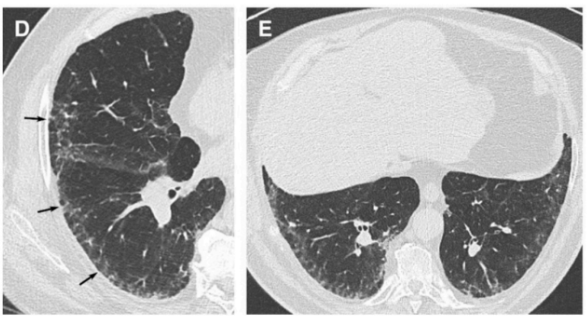

Features of Probable UIP

A

Subpleural and basal predominant

Heterogenous

+- bronchiectasis

+- mild GGO

but no honeycombing

Features intermediate UIP

Subpleural/basal predominant

Subtle reticulation

Mild GGO or distortion

features don’t suggest any specific aetiology